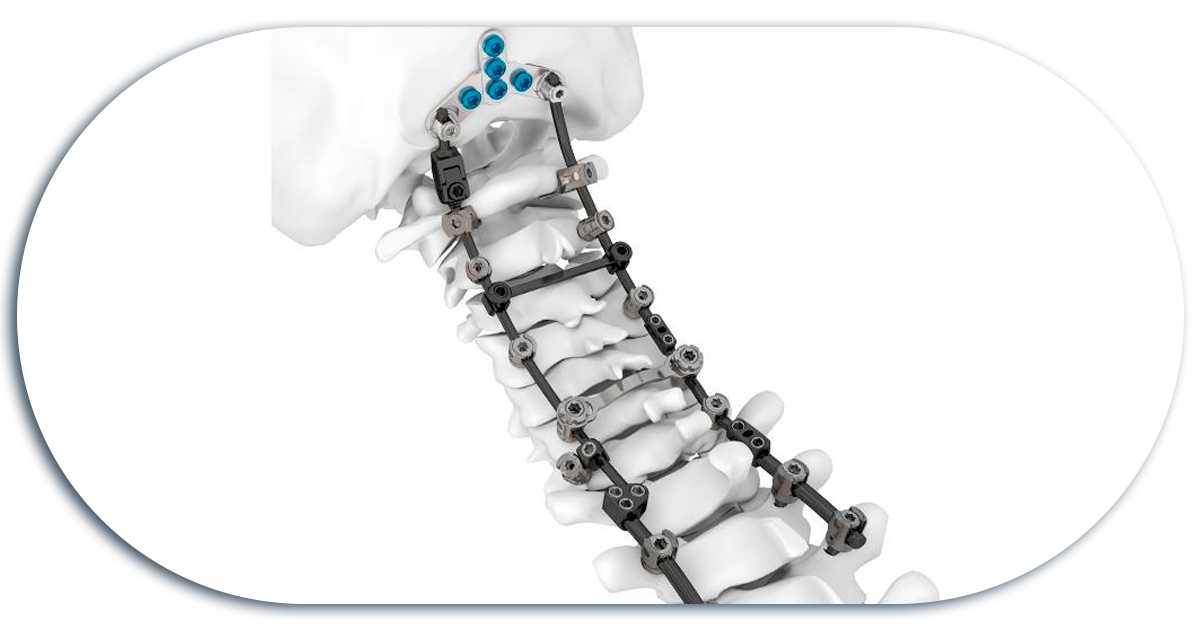

Fijacion Cervical Posterior

Se utilizan tornillos que se colocan en unas estructuras óseas llamadas facetas y estos tornillos a su vez se fijan entre sí con barras longitudinales